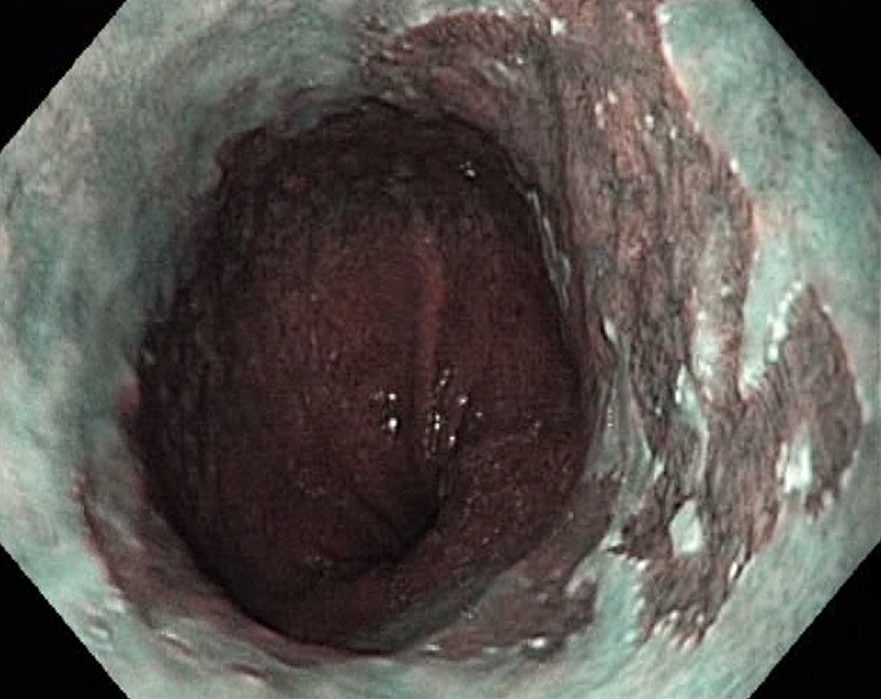

Barrets Oesophagus (NBI, Narrow Band Imaging)